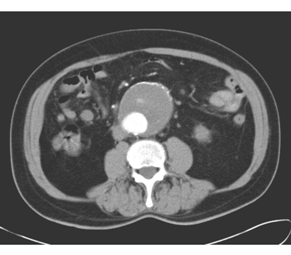

患者,男,65岁。行腹部CT增强扫描,发现腹主动脉异常,如下图:

3.本例应诊断为

A.主动脉夹层动脉瘤

B.主动脉硬化

C.主动脉血栓形成

D.主动脉瘤

E.主动脉破裂

4.对该病术前评价和术后随访的最佳方法是

A.X线平片

B.DSA

C.MSCTA

D.超声

E.MRI

正确答案:3.D;4.C